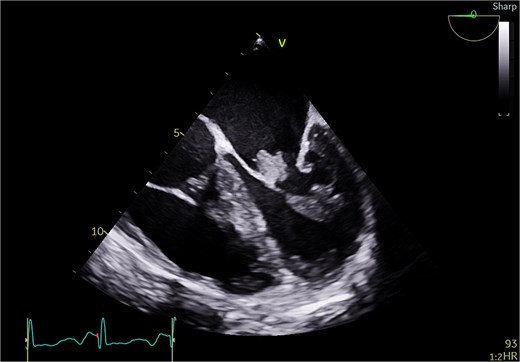

A 51-year-old woman with history of hypertension, hyperlipidemia, diabetes mellitus type II, previous ablation for supra ventricular tachycardia with implantation of loop recorder and sleeve gastrectomy for obesity was referred for surgical evaluation of MR. She was non-smoker with positive family history of ischemic heart disease affecting her mother. She was investigated for recurrent strokes with left sided paresthesia in 2022 and right sided paresthesia with dysarthria in 2024. She had dyspnea on minimal exertion and lower limb edema but no hemoptysis. She had one miscarriage previously with no history of deep vein thrombosis or pulmonary embolism. She had no history of myalgia, arthralgia, and no photosensitivity. Transthoracic echocardiography (TTE) showed pulmonary hypertension with moderate tricuspid regurgitation (TR) and moderate to severe MR and severe mitral stenosis (MS). The appearance was suggestive of rheumatic disease (Fig. 1). Trans esophageal echocardiography (TEE) showed severely dilated left atrium (LA) with no thrombus. Mitral valve with thickened with tethered posterior leaflet with mean gradient (MG) of 13 mmHg. Severe MS and moderate MR with large mass attached to the posterior scallops (Fig. 2) measuring 20 × 15 mm (likely thrombus). Ejection fraction was 55%. She was in sinus rhythm persistently and afebrile. Coronary angiography was normal. She was commenced on oral anticoagulation (Warfarin) for the possible thrombus, and she was reluctant for surgery. Her blood work was normal including normal complete blood count and renal, liver, and thyroid profile with therapeutic international normalized ratio (INR). Blood cultures were negative for growth. She was seen by haematology and work up revealed APS with a recommendation for lifelong warfarin. Patient subsequently accepted surgery.

Transesophageal echo appearance of mass attached to posterior leaflet of mitral valve (mid esophageal 4 chamber view).